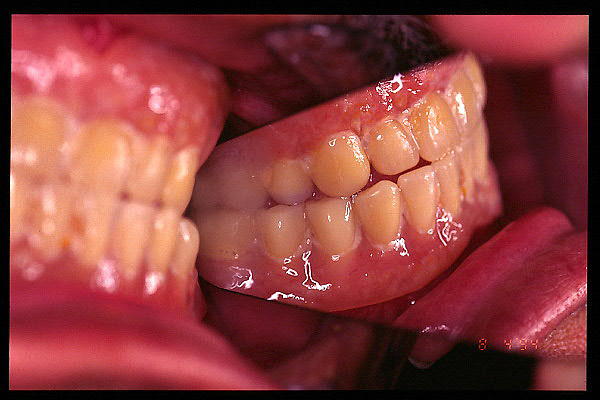

CM Caries y enfermedad periodontal avanzada